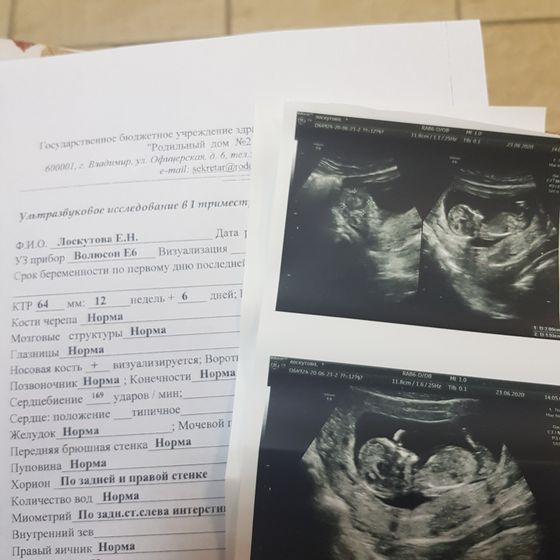

Вчера была на 1ом скрине. Все хорошо) Ребенок активный. Немного опережает развитие. Пол не сказали(( спросила «а там видно кто?» В ответ резко «нет». Я так полагаю она даже и не пыталась посмотреть))) ну да ладно. Главное что с ребенком все хорошо. Результаты крови скажут только на приёме у гинеколога.